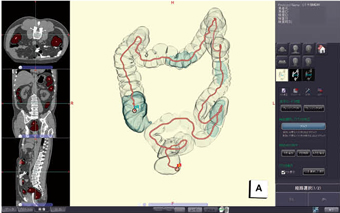

![[A01916512]アフェレシスマニュアル 改訂第3版 (クリニカルエンジニアリング別冊)](https://auctions.c.yimg.jp/images.auctions.yahoo.co.jp/image/dr000/auc0512/user/edc343cdefc90ed400aee3f558c4826ff1d13873ed0e7cf61e9f955abed75d52/i-img351x500-17335024600216yfvgi824426.jpg)

![[A11379041]脳静脈エッセンス: 脳静脈の歩き方](https://auctions.c.yimg.jp/images.auctions.yahoo.co.jp/image/dr000/auc0101/user/edc343cdefc90ed400aee3f558c4826ff1d13873ed0e7cf61e9f955abed75d52/i-img841x1200-17361951692372guhqaf576010.jpg)

![[A11992816]胃と腸 2020年 5月号増刊号 特集 消化管腫瘍の内視鏡診断2020](https://auctions.c.yimg.jp/images.auctions.yahoo.co.jp/image/dr000/auc0511/user/edc343cdefc90ed400aee3f558c4826ff1d13873ed0e7cf61e9f955abed75d52/i-img354x500-17309766305752zigk8k12685.jpg)

![[A12316613]眼科スゴ技 白内障手術: WEB動画付き 75本 第一線で活躍するサージャンの手技、最新デバイスがわかる! (眼科グラフィック2](https://auctions.c.yimg.jp/images.auctions.yahoo.co.jp/image/dr000/auc0507/users/d4fab30473777a8019148ae00533fa27693af6d4/i-img916x1200-1721998410zgg9dw204786.jpg)